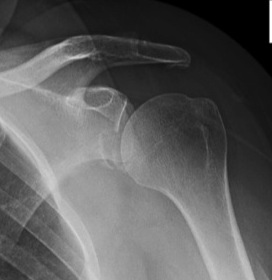

Latarjet / Bristow

Bristow

Concept

Non-anatomical bony block

- transfer of coracoid process through subscapularis

- dynamic anteroinferior musculotendinous sling

- provides subscapularis tenodesis

- preventing lower portion from displacing proximally as arm abducted

- when shoulder in vulnerable position abduction and ER